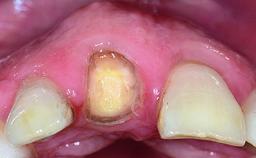

Replacement of a Missing Upper Left Central Incisor, Late Placement of an RC Bone Level Implant and Adjacent Tooth Restoration

A healthy 38-year-old male patient was referred for replacement of a failing tooth-supported cantilever fixed dental prosthesis on teeth 11 and 21. The patient reported a history of trauma at 13 years of age that had resulted in the subsequent loss of tooth 11, as well as endodontic treatment of the adjacent abutment tooth 21. A metal-ceramic cantilever fixed dental prosthesis replacing tooth 11 had been provided by his general dentist several years after the loss of the tooth, with tooth 21 as the sole abutment. At the time of initial presentation, this restoration had been in service for over 20 years.